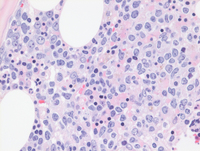

Figure 2: Bone marrow H&E in IVLBCL

The bone marrow core biopsy shows multifocal abnormal lymphoid infiltrate with a prominent sinusoidal infiltrating pattern (at higher power).